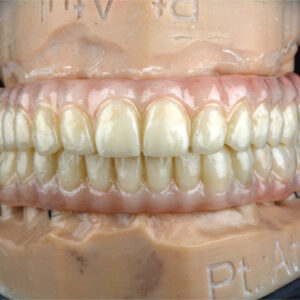

A digital denture is a modern dental prosthesis created using advanced digital technology, including 3D imaging, CAD/CAM (computer-aided design and manufacturing) and 3D printing. Digital dentures offer improved accuracy, comfort, and aesthetics compared to traditional dentures. They also reduce the number of visits required and the overall treatment time.